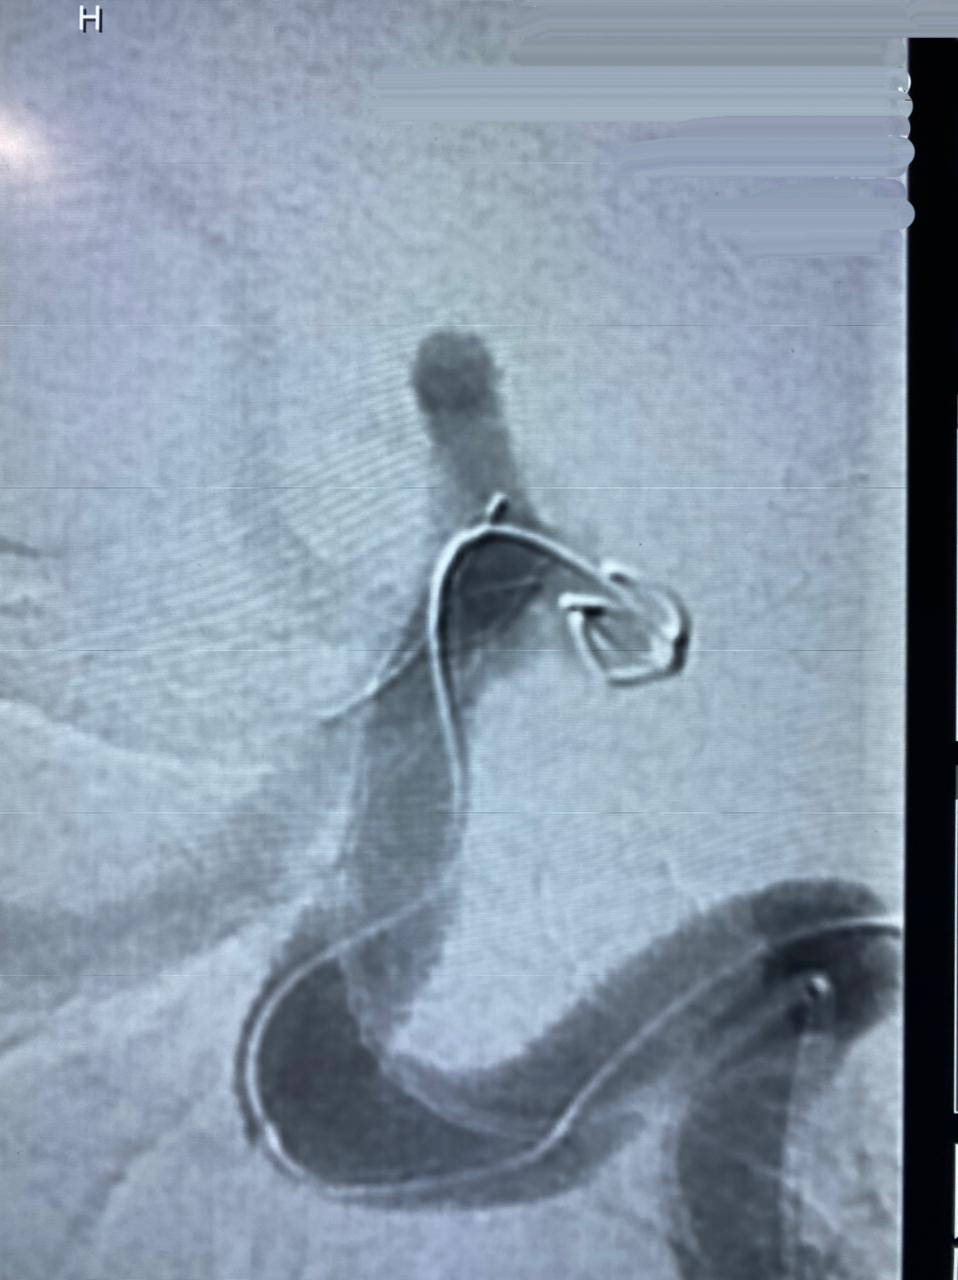

HCorBJ realiza procedimento de Embolização de Aneurisma Cerebral

O procedimento de Embolização de Aneurisma Cerebral é realizado no Setor de Hemodinâmica, sob anestesia geral, com um aparelho de imagem de última geração. O tratamento endovascular, é uma opção minimamente invasiva para as doenças cerebrovasculares.

“O primeiro caso de Embolização de Aneurisma Cerebral em Ponta Grossa, com stent diversor de fluxo, foi realizado no Hospital do Coração Bom Jesus em dezembro de 2018, o HCorBJ tem estrutura excelente para isso, tanto para realização do método, quanto no atendimento pós- operatório dos pacientes na Unidade de Terapia Intensiva (UTI) e enfermaria, com equipes altamente especializadas”, ressalta Sabatini.